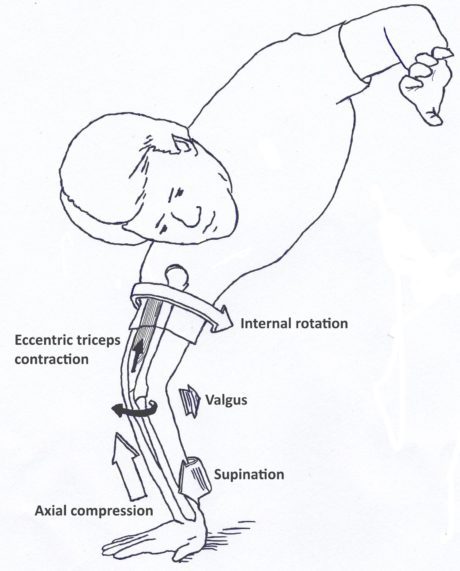

Albuen er det led i kroppen, der næst efter skulderen oftest går af led. PLRI er den mest almindelige form for albueinstabilitet som følge af en overrivning af det laterale kollaterale ligamentkompleks. Dette fører til posterolateral rotatorisk subluksation af ulna og radius.Det opstår typisk som følge af et fald på den udstrakte hånd, hvilket genererer en aksial belastning, valguskraft og en ekstern rotationsbevægelse omkring underarmen i forhold til overarmsbenet.

Det får det radiale hoved og den proksimale ulna til at subluksere posterolateralt væk fra humerus på en roterende måde, der løsner eller river det laterale kollaterale ligamentkompleks (LCL)(Camp et al. 2017).